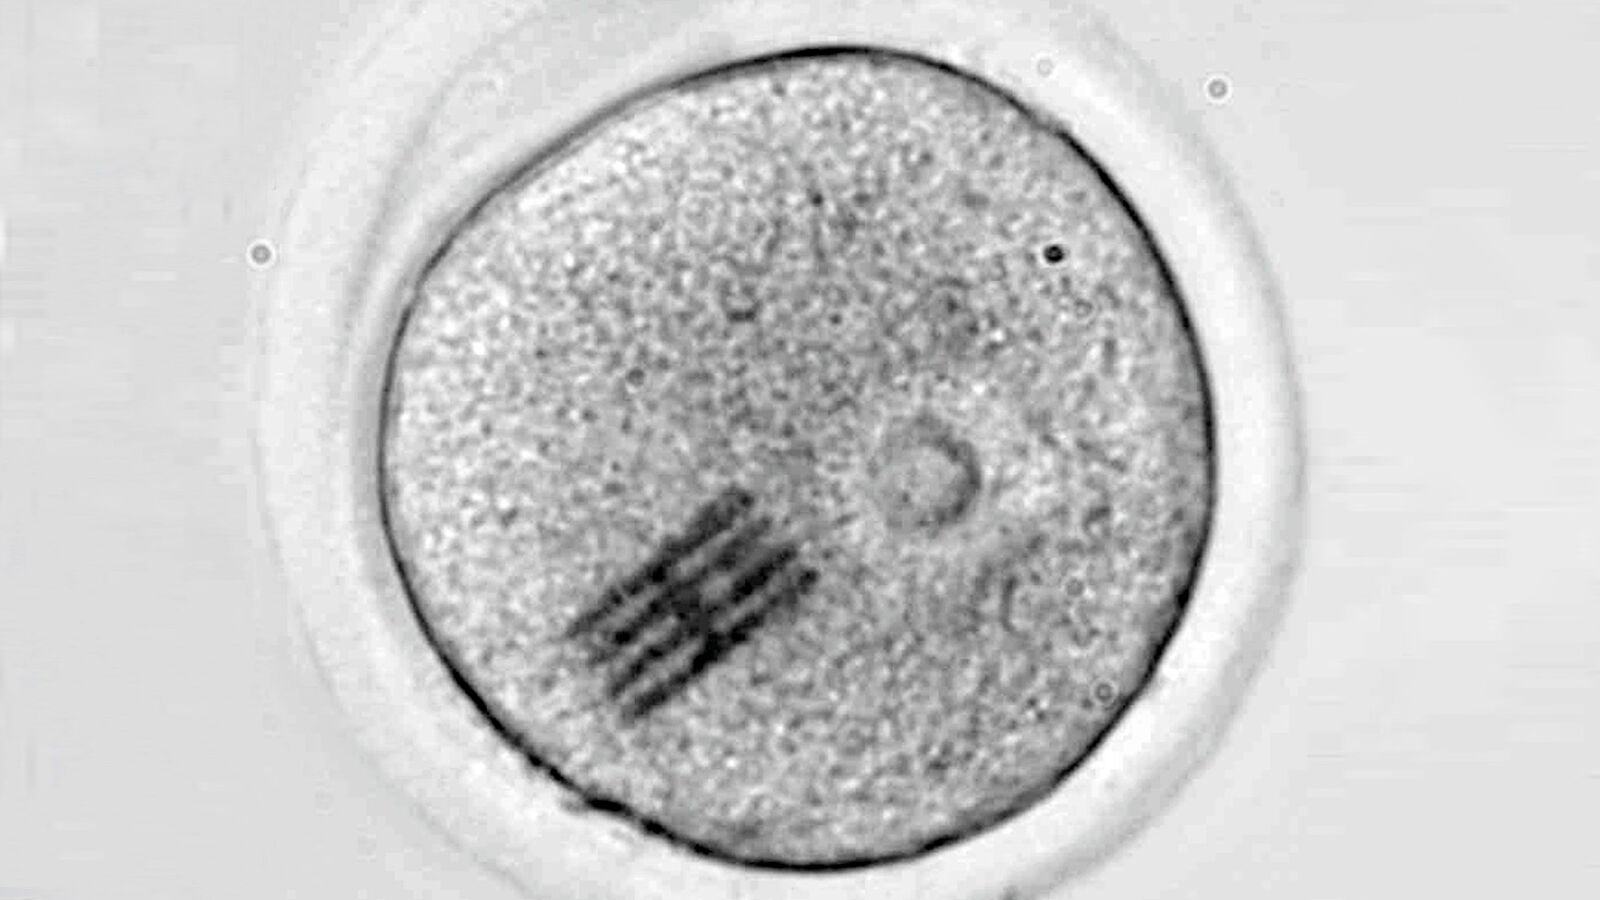

Los análisis se realizaron mediante microscopía infrarroja por láser (LDIR), tras un proceso de mineralización para eliminar componentes orgánicos. Como medida de control, se verificó que los recipientes utilizados no estaban contaminados previamente.